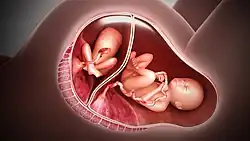

Pour les obstétriciens, l'élément déterminant à prendre en compte n'est pas la « zygosité », mais la « chorionicité » qui dépend du type et du nombre de masses placentaires. Il existe alors non pas deux types de grossesse gémellaire (monozygote et dizygote) mais trois[1],[2]:

- Grossesse bichoriale-biamnotique (près de 77 % des cas de grossesses gémellaires) : chaque fœtus a son propre chorion et son propre amnios (deux placentas et deux poches des eaux séparés).

- Grossesse monochoriale-biamnotique (autour de 20 %) : placenta commun avec deux poches des eaux séparées.

- Grossesse monochoriale-monoamniotique (2 à 3 %) : un seul placenta et une seule poche des eaux.